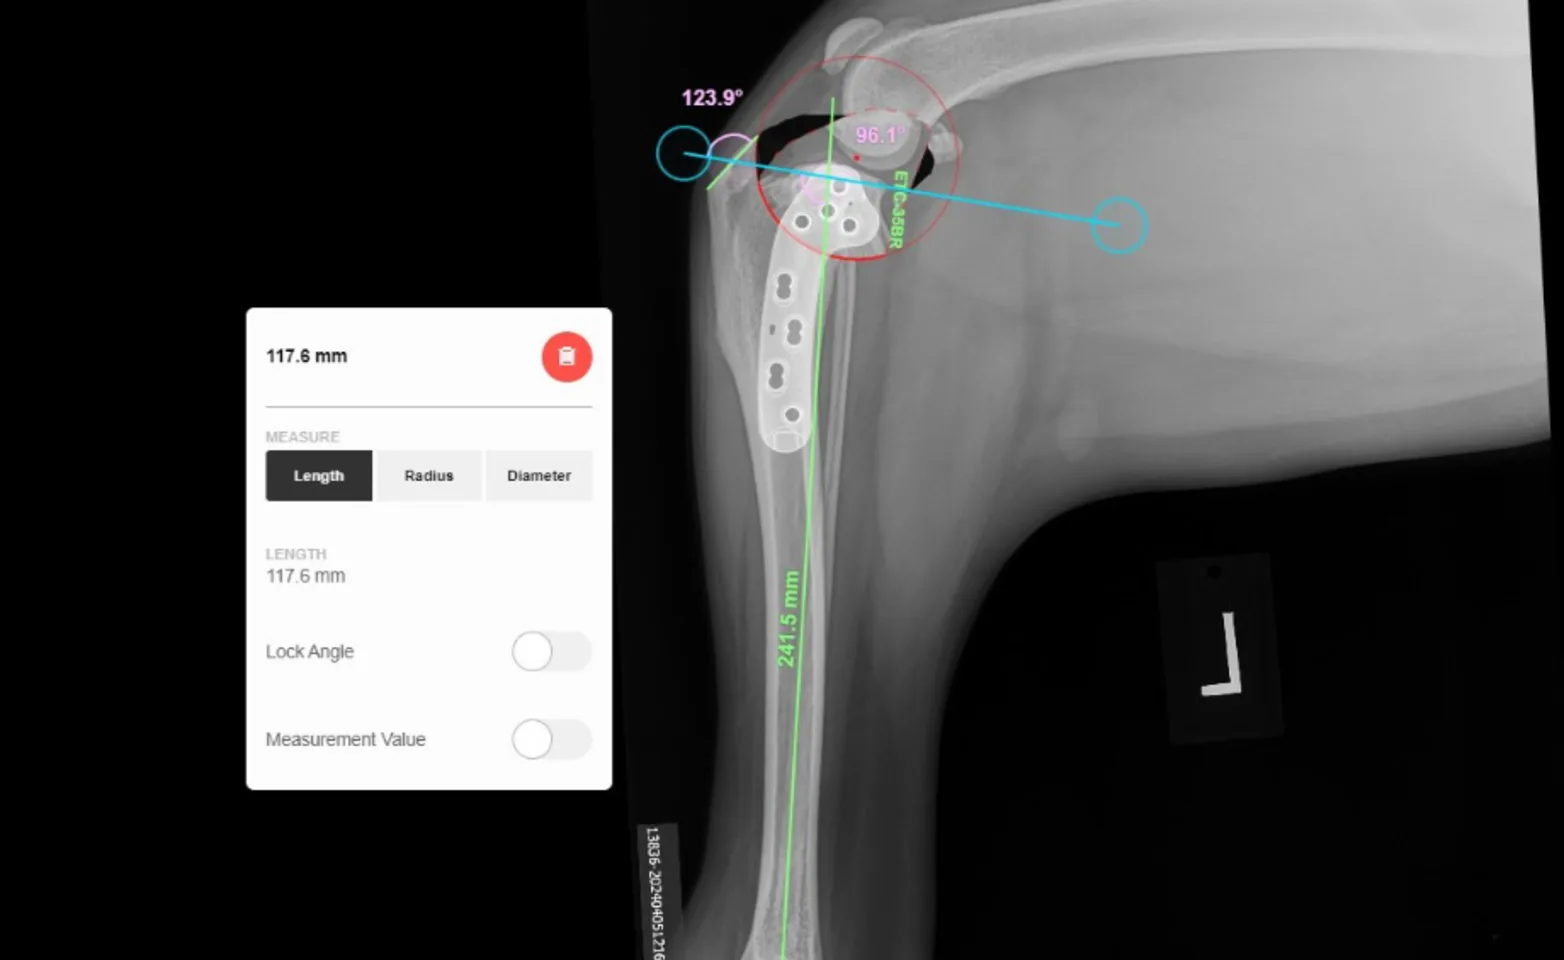

Tibial plateau leveling osteotomy (TPLO) is the recommended procedure for effectively repairing your dog’s knee injury. We have found that this surgical procedure has a higher success rate and using cutting-edge laser technology to perform this surgery offers a number of benefits. Your pet’s surgeon will surgically cut the bone (osteotomy) in the tibial plateau and then rotate the contact surface of the tibia, thereby reorienting the bone and stabilizing the stifle joint. Of course, your vet will explain your pet’s procedure in greater detail, but this gives you a general idea of the procedure itself.